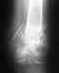

Доброго! Наступил на скользкий склон. Стопа вывернулась наружу. Перелом малоберцовой в н-3, разрывы связок, видимо. Стопу вправили в больнице. Обязательно ли оперировать?

Синдезмоз явно разорван, связки, видимо, тоже.Мнения врачей разделились. Одна группа сказала операция нужна, вторая группа склоняется к консервативному лечению. По мнению одних вывих вправили хорошо, по мнению других - нет.Прилагаю рентгены.Сейчас в гипсе, но очень переживаю за последующее состояние сустава. За т.н. "вилку"s019.radikal.ru/i626/1608/44/415179f9e5c7.jpghttp://s020.radikal.ru/i706/1608/be/6e18d02f3f13.jpgСейчас 3 недели после травмы. Одни хирург шутит, что он может мне мне сделать операцию, если я сильно захочу, но не видит особой необходимости в ней. На мои вопросы почему литература пишет, что в таких случаях операция обязательна он отвечает, что не всем повезло так поставить кости после травмы. Смущает, что при рентгене с 15градусным подворотом ноги вилка разошлась по сравнению со здоровой ногой. Прошу мнений. Спасибо.